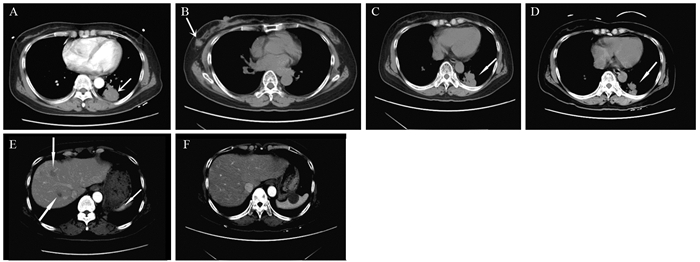

在ST-PACS医学图像工作站(北京思创贯宇科技开发有限公司)上选取肿瘤最大层面相邻的三个层面,利用自由形标记工具在ADC图上手工绘制ROI,在b=1 000s/mm2下测量平均ADC值(ADCmean)、最小ADC值(ADCmin),每个层面测量3次,并计算平均值。相对ADC值(rADC)=瘤体区ADC值/对侧脑白质ADC值,见图 1。

![]() 图 1 少突胶质细胞瘤(WHOⅢ级;IDH-1突变/1p19q共缺失)MRI和病理学表现Figure 1 MRI and pathological manifestations of oligodendrocytoma (WHO gradeⅢ) with IDH-1 mutation/1p19q co-deletionA, B: the lesions in the right temporal-parietal lobe showed heterogeneous low signal and high signal on T1WI and T2WI, respectively; C, D: DWI presented as an inhomogeneous equal-slightly higher signal (mild diffusion restricted) (C) and ADC map showed an inhomogeneous low-slightly higher signal (D); E: the measurement method of ADC value to select three ROI (10-20 mm2) in lesions and take their average values as well as select the contralateral normal brain white matter to calculate rADC; F: tumor cells were arranged in diffuse pieces, the nucleus with obvious atypia was large, and numerous necrotic regions were found in the lesions (HE ×200).

图 1 少突胶质细胞瘤(WHOⅢ级;IDH-1突变/1p19q共缺失)MRI和病理学表现Figure 1 MRI and pathological manifestations of oligodendrocytoma (WHO gradeⅢ) with IDH-1 mutation/1p19q co-deletionA, B: the lesions in the right temporal-parietal lobe showed heterogeneous low signal and high signal on T1WI and T2WI, respectively; C, D: DWI presented as an inhomogeneous equal-slightly higher signal (mild diffusion restricted) (C) and ADC map showed an inhomogeneous low-slightly higher signal (D); E: the measurement method of ADC value to select three ROI (10-20 mm2) in lesions and take their average values as well as select the contralateral normal brain white matter to calculate rADC; F: tumor cells were arranged in diffuse pieces, the nucleus with obvious atypia was large, and numerous necrotic regions were found in the lesions (HE ×200).1.4 统计学方法